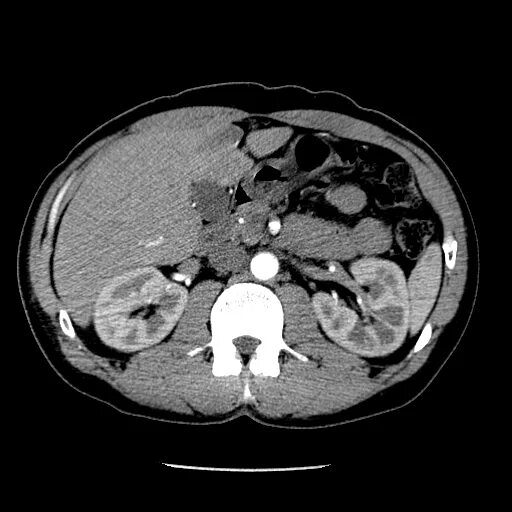

Образования печени кт